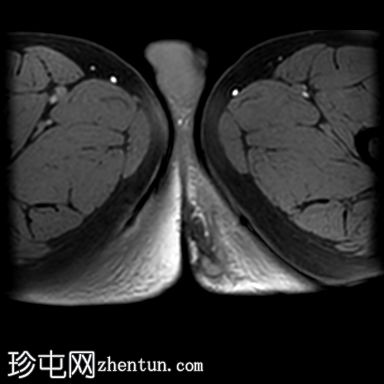

轴位T2加权像

脂肪抑制像

一条低T1信号、高T2/PD信号的弧形瘘管连接肛门黏膜和左侧会阴皮肤,并伴有明显的管状强化。该瘘管从肛门黏膜后方6点钟方向穿过肛门内括约肌,然后穿过括约肌间隙,但未穿过肛门外括约肌。皮下少量积液提示脓肿形成。上述影像学表现符合2级括约肌间肛周瘘。

根据圣詹姆斯大学医院的分类,这是一例活动性 2 级括约肌间肛周瘘 1 型病例。